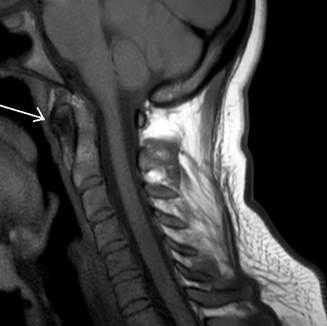

На мр-томограммах выявлялась расщелина (незаращение) передней дужки атланта, определялись особенности анатомического строения и особенности контуров передней дужки атланта в каждой из стандартных проекций (рис. 2).

Рис. 2. Коронарный и сагиттальный срезы Т2ВИ (стрелкой указаны поверхности расщепленной передней дужки)